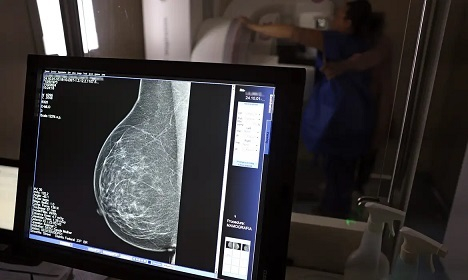

Falta de acesso a mamógrafos limita prevenção do câncer de mama

No mês de conscientização sobre o câncer de mama, um relatório destaca a importância de acesso igualitário ao rastreamento e tratamento da doença. Segundo o Atlas da Radiologia no Brasil, do Colégio Brasileiro de Radiologia e Diagnóstico por Imagem (CBR), o acesso aos mamógrafos ainda é um desafio.

O país tem 6.826 equipamentos registrados, sendo 96% em funcionamento. Metade deles está disponível no Sistema Único de Saúde (SUS), responsável por atender 75% da população. Isso equivale a 2,13 mamógrafos por 100 mil habitantes dependentes do SUS.

Na saúde suplementar, que cobre 25% da população, o cenário é mais favorável: 6,54 aparelhos por 100 mil beneficiárias, quase o triplo da rede pública. O Acre exemplifica essa disparidade — são 35,38 mamógrafos por 100 mil habitantes na rede privada, contra 0,84 no SUS.

O Brasil tem uma cobertura muito baixa de mamografias: 24%. O ideal recomendado pela Organização Mundial da Saúde é de 70%. Mesmo em lugares como o estado de São Paulo, que tem a maior concentração de mamógrafos do país, a taxa gira em torno de 26%.

Em setembro, o Ministério da Saúde ampliou as diretrizes de rastreamento, recomendando que mulheres entre 40 e 49 anos realizem mamografias, mesmo sem sintomas. De acordo com o Instituto Nacional do Câncer (Imca), mais de 73 mil mulheres recebem o diagnóstico de câncer de mama anualmente no Brasil.